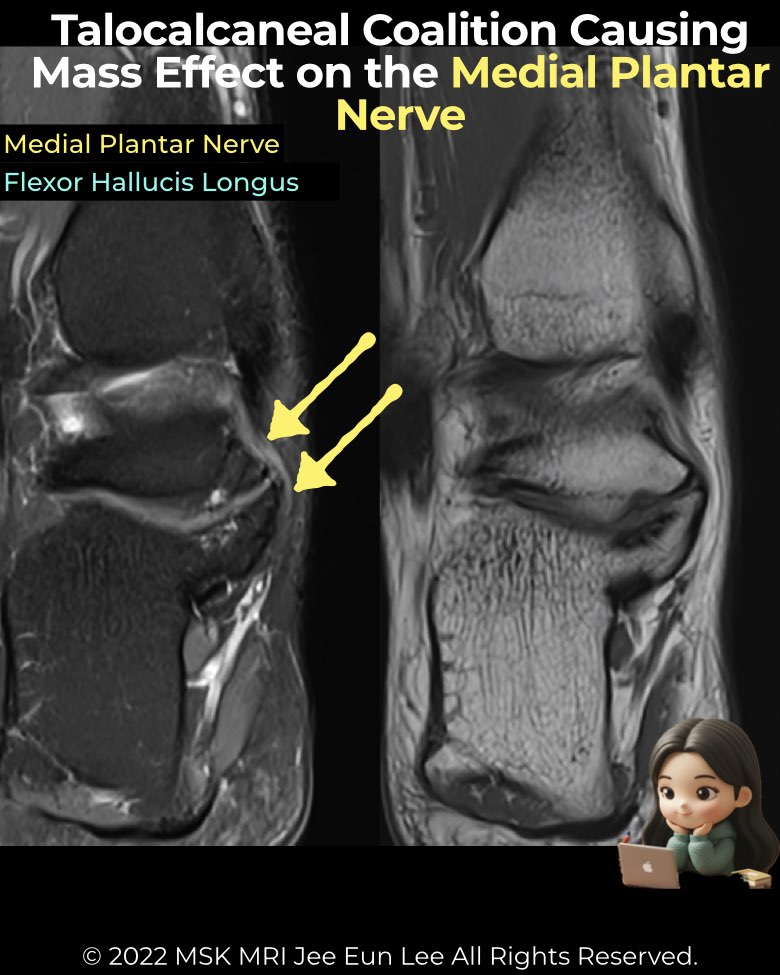

Tarsal coalitions, especially talocalcaneal types, can produce mass effect in the tarsal tunnel, leading to nerve and tendon pathology.

- Bony overgrowth from fibrous/cartilaginous coalitions (often EA-PM or middle facet) protrudes into the tunnel.

- The medial plantar nerve (MPN) is most frequently affected due to its close course along the medial talus/calcaneus.

- MRI findings of neuritis:

• Focal T2 hyperintensity (equal to or > blood vessels)

• Caliber enlargement

• Direct abutment/displacement by coalition or cyst